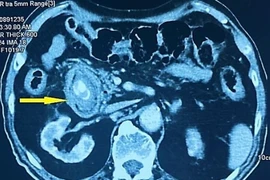

Bệnh viện Trung ương Quân đội 108 vừa phẫu thuật lấy gần 300 viên sỏi trong túi mật của người phụ nữ 61 tuổi, may mắn chưa biến chứng xuống ống mật chủ.